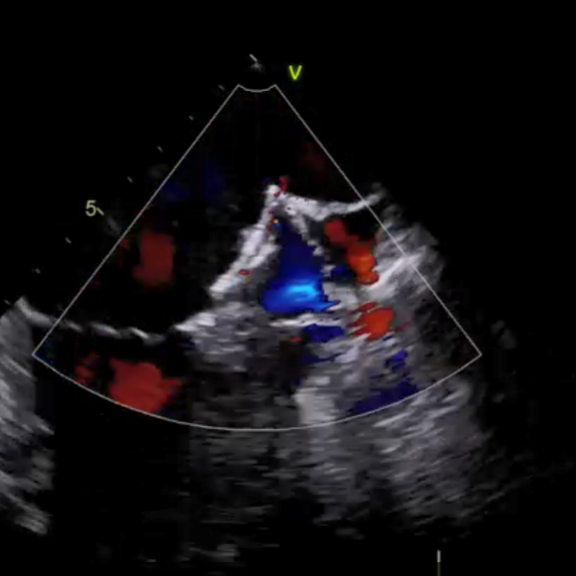

如图3所示,术中造影显示患者的左心耳固定区尺寸为23mm、深度25mm,选用规格为锚定盘直径26mm,密封盘直径 31 mm的左心耳消融封堵器植入到左心耳内。如图4-5所示,消融前后采用德诺电生理标测导管对左心耳进行电信号检测,对比结果表明左心耳电信号完全隔离;如图6所示,术者分别在左心耳消融前后进行了冠状动脉造影,造影显示回旋支无明显变化,无痉挛等不良事件发生;如图7-8所示,封堵器解脱前对左心耳消融封堵器进行了牵拉测试,器械无移位,造影及TEE超声显示左心耳完全封堵,无残余分流。

图7 左心耳封堵器牵拉测试

(a)DSA造影显示封堵良好

(b)TEE无残余分流

图8 左心耳封堵器封堵DSA和TEE影像